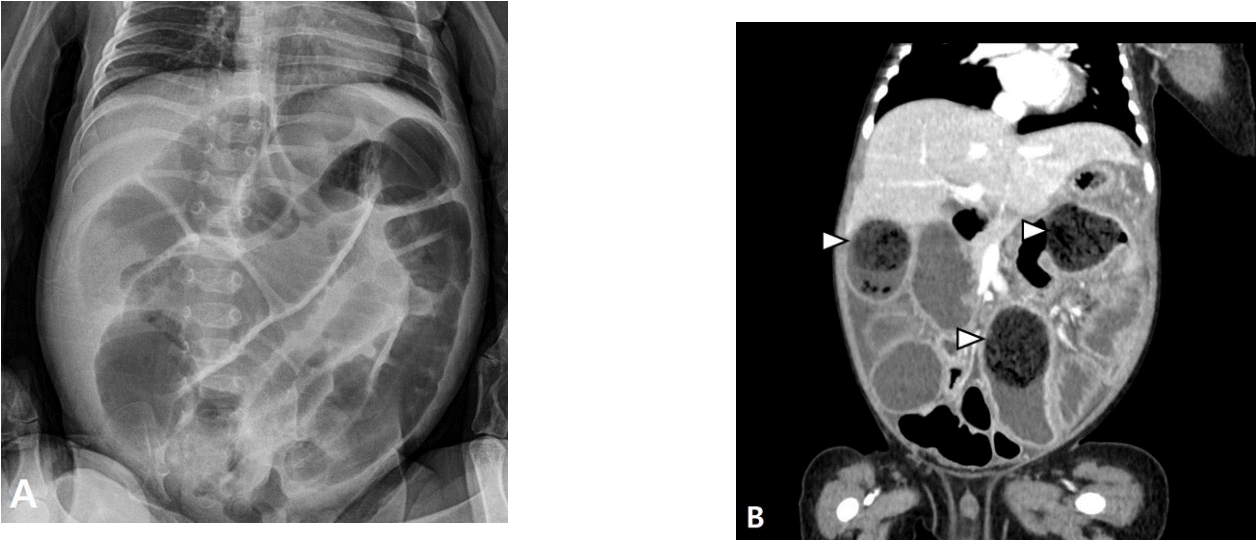

An initial abdominal plain radiograph showed diffuse dilatation of bowel loops (Fig. 1A). Initial laboratory findings were as follows: leukocytes, 18,700/µL (neutrophils, 57.6%); hemoglobin, 9.8 g/dL; platelets, 615,000/µL; sodium, 132 mmol/L; potassium, 5.0 mmol/L; albumin, 2.7 g/dL; blood urea nitrogen, 12.5 mg/dL; creatinine, 0.14 mg/dL; and C-reactive protein, 20.8 mg/dL. A computed tomography demonstrated a total of 3 bezoars (diameters: 4.1, 3.5, and 3.3 cm) causing small bowel obstruction, without evidence of malrotation, stricture, or stenosis (Fig. 1B).

Fig. 1.

Plain radiographs of the infant’s abdomen. An initial radiograph shows the diffuse dilatation of small bowel loops (A). A computed tomography scan shows the presence of 3 particulate feculent materials mingled with gas bubbles in the lumen of the dilated small bowel loops, indicating the bezoars (B, arrowheads).